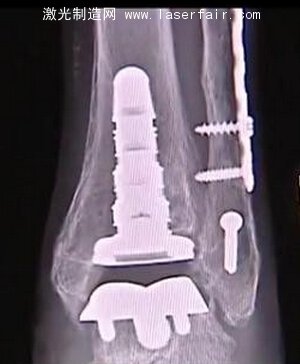

德州醫(yī)生成功完成3D打印踝關節(jié)置換手術

一個名叫Bettye Dube的女人應當感謝3D打印技術應用帶給她的幫助。Dube當初在牙買加度假時不幸跌倒,導致她的腳踝粉碎性骨折。在打了幾個月的石膏,并進行廣泛的物理治療后,她的兩個腳踝變得不一樣了。于是一個朋友建議她去找Marvin Brown醫(yī)生。Brown醫(yī)生是足部、踝部和小腿關節(jié)置換的專家,他的辦公地點在德克薩斯州的San Antonio。Brown認為Dube需要做踝關節(jié)置換手術。

Brown醫(yī)生精通最新的技術,他決定使用一個相對較新的手術方法。他使用一截最先進的3D打印假肢“inbone”置換了Dube的整個腳踝。

3D打印能夠根據Dube的個人特征為其量身定做特殊的腳踝,效果要比過去的一些傳統的踝關節(jié)置換好得多。雖然Dube的腳踝不能100%地恢復到她跌倒以前的狀況,而且她再也不能穿高跟鞋,手術仍然是令人難以置信的成功。

在踝關節(jié)置換中的3D打印部分可以保持大約10年,只要Dube遵循醫(yī)生的囑咐,注意她的重量,并且穿減震的鞋子。